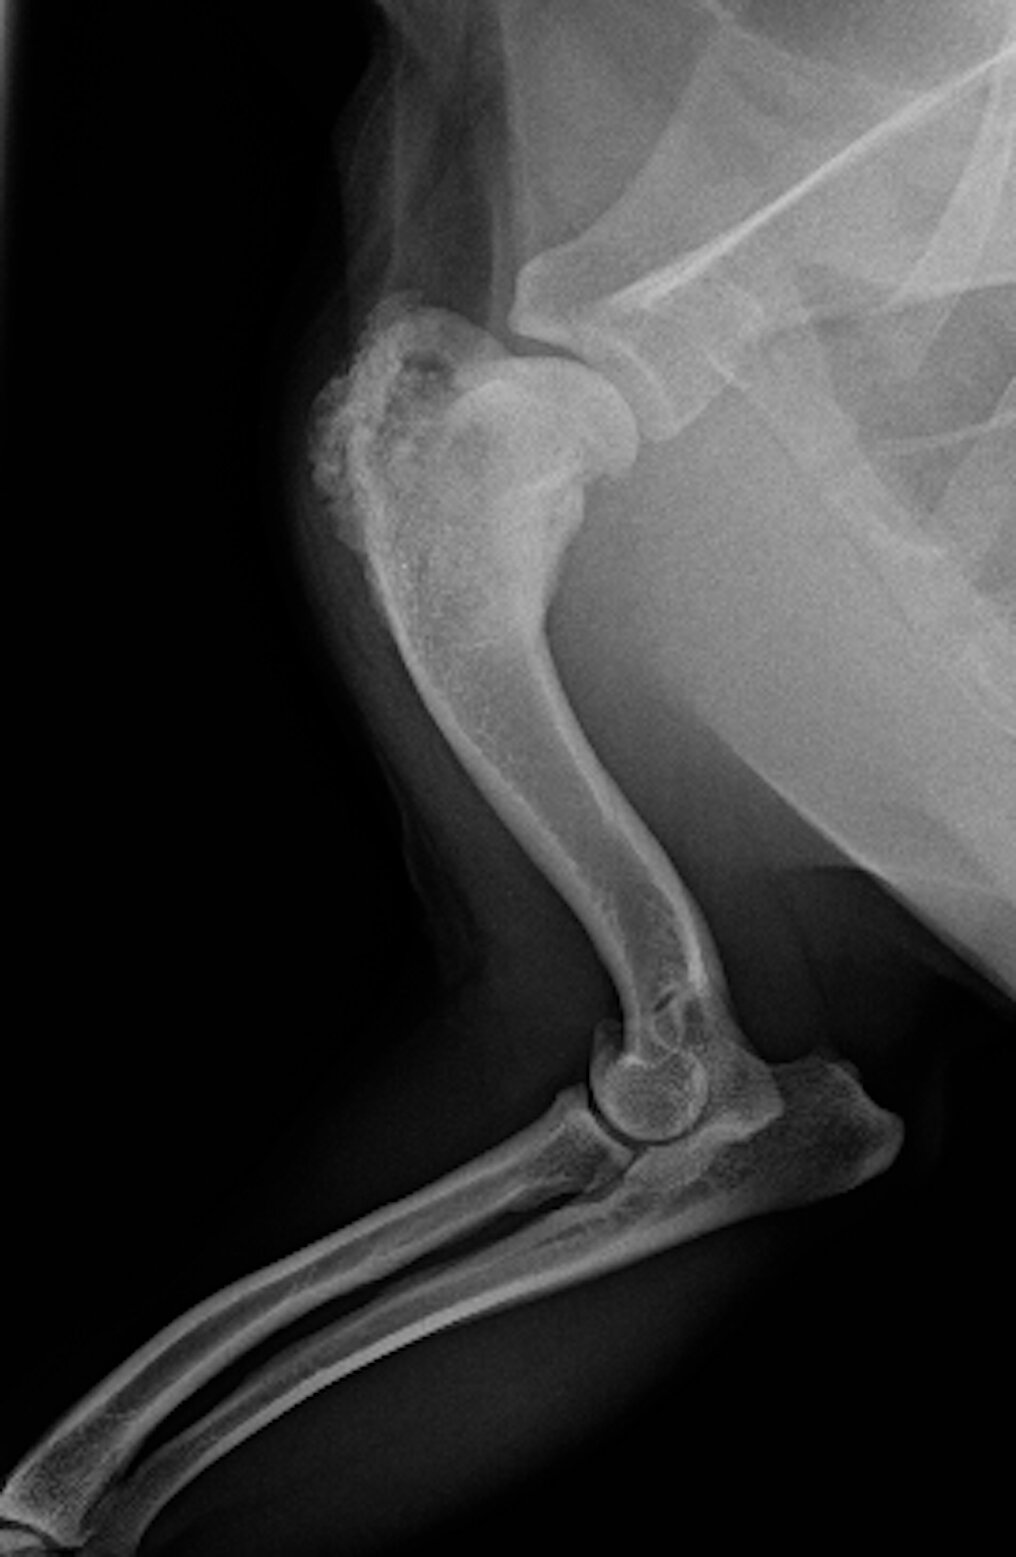

A Comprehensive Guide To Osteosarcoma In Dogs Tploinfo

Most cases of canine osteosarcoma about 90 have undergone micrometastasis by the time they are diagnosed making this type of cancer difficult to cure. Lung cancer had the lowest 1-year survival rate after bone metastasis 10 percent. Morris animal foundation makes a stand against osteosarcoma.

In the axial skeleton the tumor does not grow rapidly as do the appendicular tumors thus leading to a more insidious course of disease. The exact survival time and overall prognosis for dogs with bone cancer depend on several factors such as tumor type. How long does bone cancer take to kill a dog.